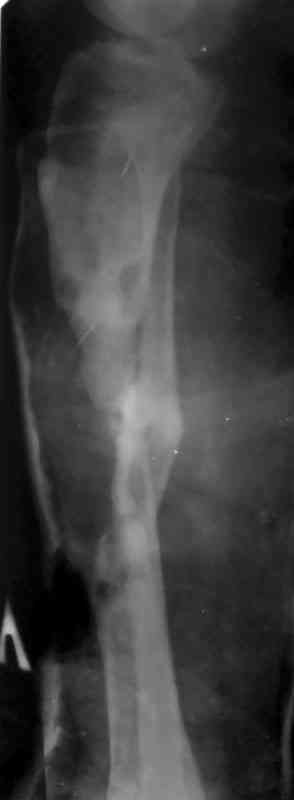

Как дополнение высылаю снимки и фото конечности, чтобы Вы могли оценить состояние м/т, и течение заболевания.

Кстати на предоперационных снимках видно, что Ваш пациент имел Сегментарный перелом на границе верхней и средней трети большеберцовой кости и средней трети большеберцовой кости. Непонятно почему был удалён средний сегмент перелома.Почему в течении такого большого времени не предпринимались попытки для замещения деффекта.

Судя по месту расположения свища, наличия литического учаска в проксимальной части дистального фрагмента на последнем снимке, и, наличие в этом месте стержня Шанца на послеоперацционном снимке, причина остеомиелита у Вашего пациента спицевая.